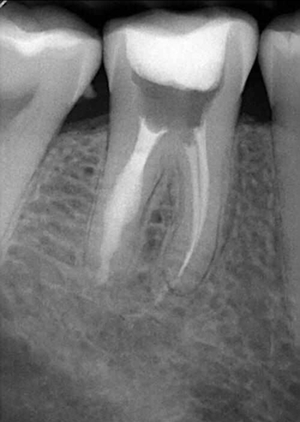

牙體吸收可分為生理性吸收和病理性吸收。如成熟乳牙的牙根吸收,即為一個生理性過程。病理性牙體吸收則包括牙外吸收和牙內吸收。牙外吸收的發(fā)生通常與根尖周病變、正畸治療和快速生長的腫瘤有關,始發(fā)部位為牙根外表面或牙頸部,吸收過程由外到內。而牙內吸收也被稱為髓腔內吸收,是指正常的牙髓組織肉芽變性,引起髓腔內部牙體硬組織吸收,并逐漸向周圍的牙本質層進展。如果未能得到及時的治療,將可能導致病變恒牙的早失。恒牙牙內吸收較為少見,且常無明顯臨床癥狀,多數(shù)病例為行常規(guī)影像學檢查時發(fā)現(xiàn)。然而,病變早期并無明顯影像學改變,這使得牙內吸收的早期診斷變得更加困難。因此,當患牙出現(xiàn)癥狀或者有影像學改變時,病變往往己發(fā)展至較嚴重階段,使得治療難度加大,遠期效果欠佳。[1]

牙內吸收通常無明顯癥狀。根據(jù)吸收的類型和原因,主要分為炎癥性吸收和替代性吸收。其中,炎癥性吸收可能繼發(fā)于前期牙本質的細菌感染和創(chuàng)傷,牙本質吸收過程的進展不伴有吸收區(qū)鄰近部位硬組織的沉積,吸收部位可見大量肉芽組織,典型的影像學表現(xiàn)為,以根管為中心的橢圓形透光區(qū)。替代性吸收,導致根管內牙本質缺損的同時,在缺損區(qū)某些部位還伴有骨樣組織的沉積,造成牙髓腔不規(guī)則的擴大和根管連續(xù)性的破壞。根據(jù)牙內吸收發(fā)生部位和嚴重程度的不同,又可呈現(xiàn)不同的征象。若吸收部位發(fā)展至牙冠,可以觀察到牙冠上出現(xiàn)粉紅色的點,這是吸收細胞鄰近的結締組織高度血管化的結果。當吸收部位位于根方,則可使得根管原有的形態(tài)缺失,X線片可見根管局部氣球樣的膨大,通常邊界清晰。若牙髓還有部分的活力,則患牙可能有慢性牙髓炎的表現(xiàn);若牙髓完全壞死,則可能發(fā)展成根尖周炎,而出現(xiàn)相應的癥狀。竇道的出現(xiàn)往往是己發(fā)生慢性根尖膿腫或根管側穿的表現(xiàn)。由于患牙冠方的牙髓通常己經(jīng)壞死或被去除,因此敏感性測試常為陰性。